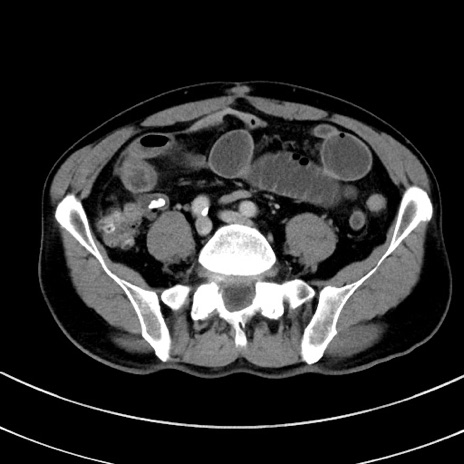

症例8(横断像)

【症例】 60歳代男性

【主訴】 黒色吐物

【現病歴】 4日前から嘔気自覚、2日前の朝食後にも嘔気あり、自分で手で嘔吐反射起こし嘔吐したところ血が混ざっていたため受診。

【既往歴】 5年前汎発性腹膜炎を伴う急性虫垂炎で手術、高血圧、前立腺肥大症、高脂血症

【身体所見】 腹部正中に手術癩痕あり 腹部平坦・軟圧痛なし膨満感あり

【データ】WBC 8400、CRP 4.54